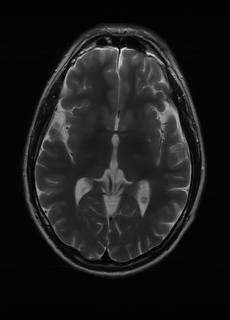

As we observe from the right image in Fig. 2, our BRM, both from MIMO and SISO settings, predicts the performance of dedicated models with a high correlation. We further choose the best three , and perform the last stage of fine-tuning accordingly to (6). A visual evaluation on real data is shown in Fig. 3. For simulated data, please refer to the Supplemental Material section.

Base on the best performing , we perceive that among , , and FLAIR, the results are best when is sampled the most. We suggest that this makes intuitive sense as images provide the best contrast out of the three sequences, which can compensate for the details lost in other images. The same observation can be made on the simulated data, where both and FLAIR show good contrast. When the time setting is changed to non-uniformity, we can see that our search for the best sampling strategy reflects the change. is sampled more as a result of faster acquisition time, while is still sufficiently sampled.

| Sequence | LR | SISO | MIMO | MIMO tuned | GT |

|---|---|---|---|---|---|

(a) 34.38/0.9371

(a) 34.38/0.9371

|

(b) 42.42/0.9883

(b) 42.42/0.9883

|

(c) 44.60/0.9920

(c) 44.60/0.9920

|

(d) 45.50/0.9940

(d) 45.50/0.9940

|

(e) PSNR/SSIM

(e) PSNR/SSIM

|

|

(f) 29.74/0.8903

(f) 29.74/0.8903

|

(g) 36.25/0.9734

(g) 36.25/0.9734

|

(h) 36.42/0.9752

(h) 36.42/0.9752

|

(i) 37.70/0.9832

(i) 37.70/0.9832

|

(j) PSNR/SSIM

(j) PSNR/SSIM

|

|

(k) 39.89/0.9311

(k) 39.89/0.9311

|

(l) 43.94/0.9864

(l) 43.94/0.9864

|

(m) 44.74/0.9883

(m) 44.74/0.9883

|

(n) 45.49/0.9894

(n) 45.49/0.9894

|

(o) PSNR/SSIM

(o) PSNR/SSIM

|